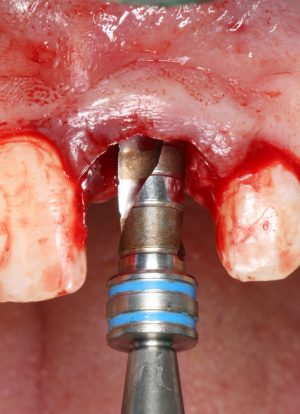

Подготовка лунок для имплантатов

Прежде, чем приступить к аугментации (пластике) лунок зубов, мы подготовили лунки для имплантатов. В таких клинических случаях нет необходимости в использовании шаблона. Вместо этого, мы применяем общепринятые правила позиционирования и соблюдаем рекомендации производителя по хирургическому протоколу:

В процессе ирригации лунки промываются, что позволило нам еще раз подтвердить ранее сделанные выводы. С помощью аналогов имплантатов, входящих в хирургический набор Xive, мы проверили возможность стабилизации имплантатов в будущих лунках. Исходя из правил подбора и позиционирования имплантатов (я очень рекомендую почитать об этом здесь>>) мы остановились на Xive S диаметром 3,4 мм и длиной 13 мм.

Подготовка двух лунок для имплантатов занимает около 10 минут.